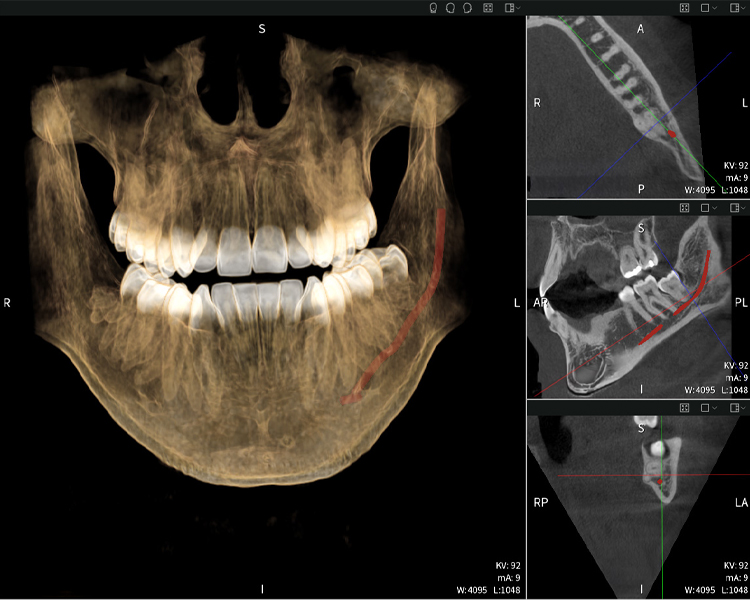

Figure e: The panoramic X-ray serves as an initial assessment tool, showing the general positioning of the teeth as well as any potential pathological changes. Notably, on the right side (tooth 48), the situation following a crown amputation performed by an external practitioner is visible. The two severely curved roots remain in close topographical proximity to the inferior alveolar nerve within the bone. This suggests a deliberate decision to avoid the increased risk of nerve injury during a complete extraction, and represents a clinically relevant finding. In summary, CBCT scans with Seethrough Max, provide crucial information about the complex anatomy and the critical relationship between the wisdom teeth and the inferior alveolar nerve. This detailed preoperative diagnostic imaging is essential for safe and successful surgical procedures in the mandibular region.